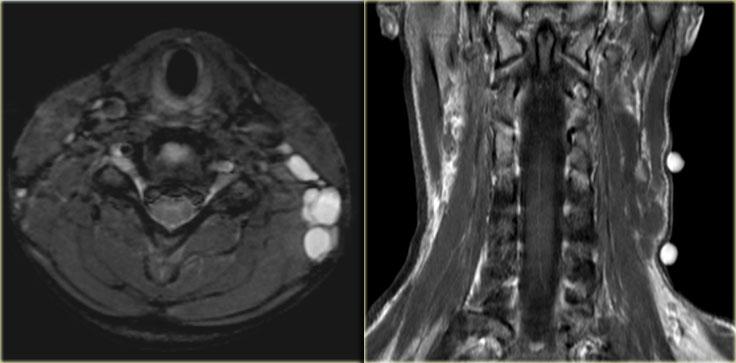

U mạch bạch huyết hay U nang bạch huyết

Bên trái là hình ảnh chuỗi xung T2W mặt phẳng axial có xóa mỡ và chuỗi xung T1W mặt phẳng coronal của một bé gái 12 tuổi đến khám vì sưng mềm ở vùng cổ.

Bước 1

Có một tổn thương đa thùy trong khoang cổ sau.

Bước 2

Phân tích các thành phần giải phẫu:

- Mô mỡ:

Hình ảnh chuỗi xung T1W mặt phẳng coronal cho thấy mô mỡ bình thường xung quanh tổn thương. - Thần kinh:

Bệnh lý thần kinh phụ hiếm gặp và thường biểu hiện là một tổn thương đặc đơn độc.

Các tổn thương đám rối thần kinh cánh tay thường nằm ở vị trí cạnh cột sống hơn. - Hạch bạch huyết:

Có thể cân nhắc, nhưng các hạch thường đặc hoặc một phần đặc.

Di tích phôi thai:

Các di tích của hệ bạch huyết nguyên thủy như u mạch bạch huyết thường gặp nhất ở nhóm tuổi này và cần được xem xét.

Bước 3

Trên chuỗi xung T2W có xóa mỡ, tổn thương có cấu trúc đa thùy với tín hiệu dịch.

Không có hình ảnh ngấm thuốc trên chuỗi xung T1W.

Những đặc điểm này, kết hợp với việc khối sưng mềm và xuất hiện ở trẻ em, là đặc trưng cho chẩn đoán u mạch bạch huyết, còn được gọi là u nang bạch huyết.